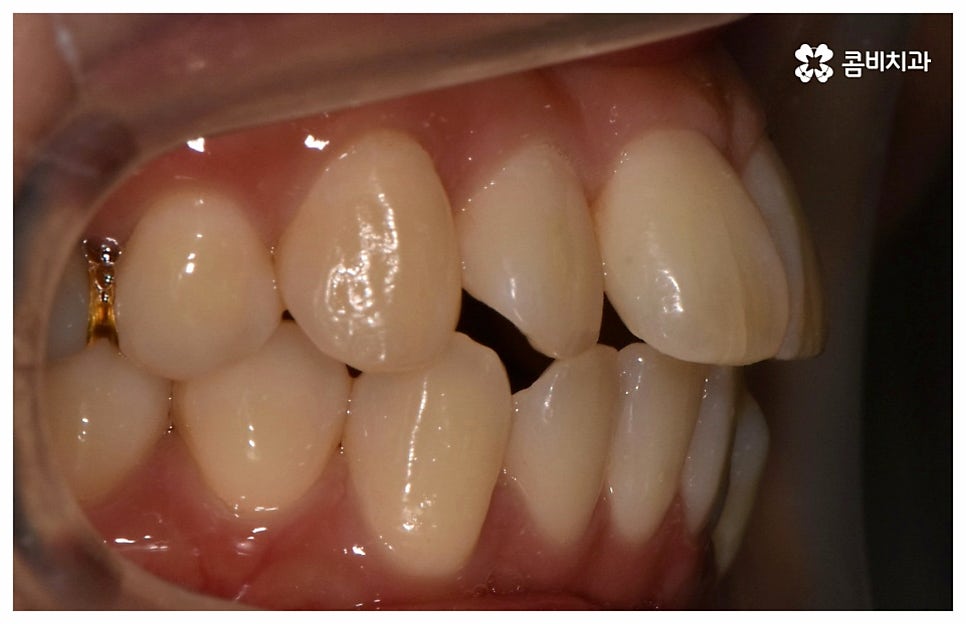

그래서인지 자기 관리의 일환으로 외모를 가꾸고 치아 건강을 증진시키기 위해 중년치아교정 을 고려하시는 분들도 늘어나고 있어요. 치열이 삐뚤어지고 교합이 잘 맞지 않는다면 교정 치료를 통해 이를 바로잡아 저작 기능을 향상시키고 발음을 정확하게 할 수 있으며, 심미적으로도 호감가는 인상을 만들고 추후 치아 관리도 보다 수월하게 할 수 있도록 도움을 받을 수 있기 때문에 이에 대한 수요가 많아지고 있는 거예요.

교정의 경우 보통 1년 반에서 2년 정도로 짧지 않은 기간이 걸리기 때문에 장치가 겉으로 드러나는 것에 대해 부담을 느끼시는 중장년분들이 많이 있습니다. 하지만 환자분들의 상황에 따라 부정 교합 정도가 심각하지 않고 골격적인 원인이 크지 않다면 6~8개월 정도 소요되는 부분 교정으로 필요한 부위만 보다 빠르고 간편하게 바로잡을 수 있으니 먼저 검진부터 진행해 보시길 권유드리고 있어요.

위 사진은 환자분의 동의를 받아 이해를 돕기 위한

사진이며, 실제 치료 결과는 다를 수 있습니다.